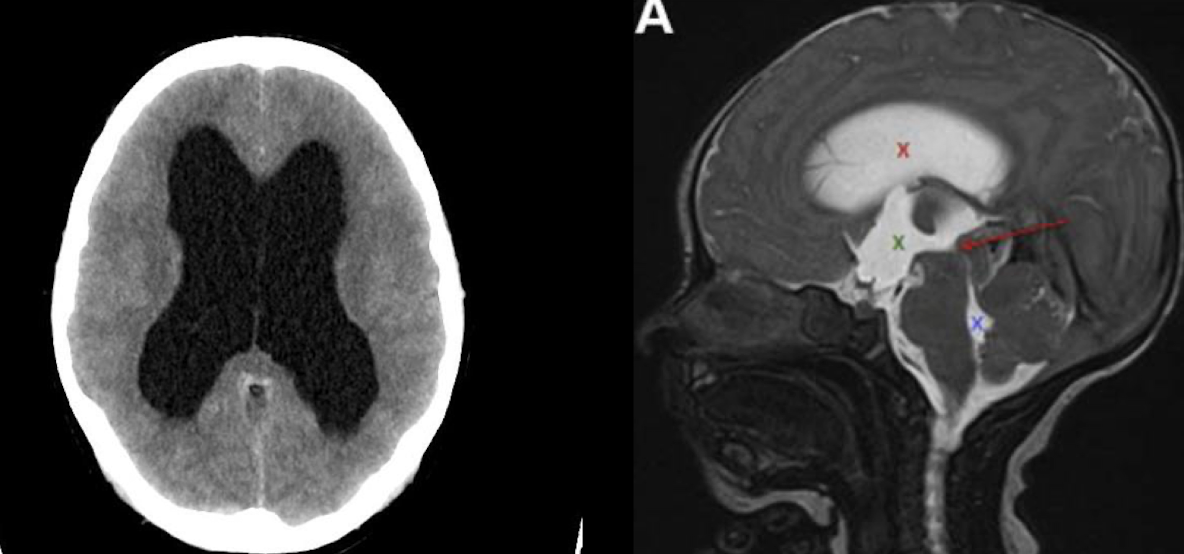

HIV/NO COM IMAGEN

A

EM, TC O USG

IN UTERO US

Us transfontalenar

RM lo mejor para ver obstr del LCR: dilatación proximal a la obstrucción

HC INTRAVENTRICULAR